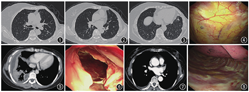

(1)临床表现:患者年龄为33~70岁,平均年龄(58±9)岁,4例为无胸腔积液患者,其余患者胸腔积液量为40~100 ml(表1)。所有患者术前均行胸部增强CT检查(表1),3例患者胸部CT及胸腔镜下表现见图1,图2,图3,图4,图5,图6,图7,图8。(2)病理结果:10例患者中,8例患者明确病理诊断(表1)。(3)并发症:1例患者发生术中切口出血(30 ml),2例患者术后切口轻微疼痛,未见大出血、中重度胸痛、气促、皮下气肿、空气栓塞等不良反应。1例脓胸患者因引流胸液引流管拔管较晚。